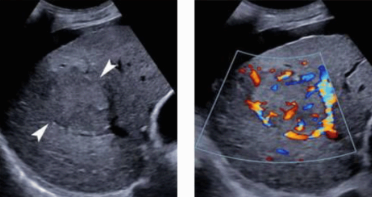

- color doppler : internal mass pattern (feeding artery)

- color doppler: basket pattern